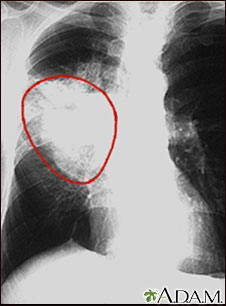

Cáncer de pulmón -Radiografía frontal del tórax

Radiografía de tórax en un paciente con cáncer en el área central del pulmón derecho. El carcinoma se presenta como una masa blanca en la parte central del pulmón derecho (al lado izquierdo de la imagen).